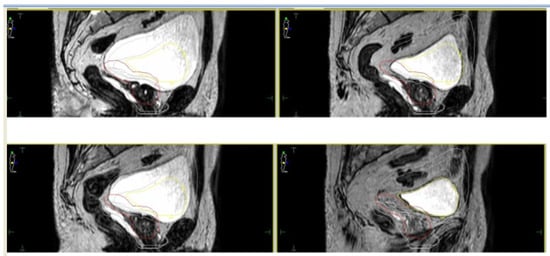

- Cuccia, F.; Mazzola, R.; Nicosia, L.; Figlia, V.; Giaj-Levra, N.; Ricchetti, F.; Rigo, M.; Vitale, C.; Mantoan, B.; De Simone, A.; et al. Impact of hydrogel peri-rectal spacer insertion on prostate gland intra-fraction motion during 1.5 T MR-guided stereotactic body radiotherapy. Radiat. Oncol. 2020, 15, 1–9. [Google Scholar] [CrossRef] [PubMed]

- Alongi, F.; Rigo, M.; Figlia, V.; Cuccia, F.; Giaj-Levra, N.; Nicosia, L.; Ricchetti, F.; Vitale, C.; Sicignano, G.; De Simone, A.; et al. Rectal spacer hydrogel in 1.5T MR-guided and daily adapted SBRT for prostate cancer: Dosimetric analysis and preliminary patient-reported outcomes. Br. J. Radiol. 2021, 94, 20200848. [Google Scholar] [CrossRef] [PubMed]

- Ardekani, M.A.; Ghaffari, H.; Navaser, M.; Moghaddam, S.H.Z.; Refahi, S. Effectiveness of rectal displacement devices in managing prostate motion: A systematic review. Strahlenther. Onkol. 2021, 197, 97–115. [Google Scholar] [CrossRef] [PubMed]

- De Leon, J.; Jameson, M.G.; Rivest-Henault, D.; Keats, S.; Rai, R.; Arumugam, S.; Wilton, L.; Ngo, D.; Liney, G.; Moses, D.; et al. Reduced motion and improved rectal dosimetry through endorectal immobilization for prostate stereotactic body radiotherapy. Br. J. Radiol. 2019, 92, 20190056. [Google Scholar] [CrossRef]